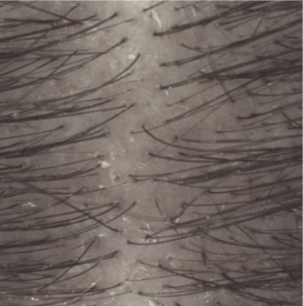

Efficacy results

Induration at 1 month (3).

(1) Clinical study on 54 subjects with light to moderate psoriasis on the scalp. 4 week attack phase: 3 shampoos per week

(3) Clinical assessment of plaque induration at D29.